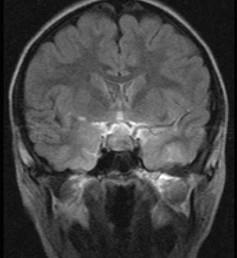

鞍区占位病变(见图)引的典型视野障碍是()A.双眼颞侧偏盲B.象限盲C.一侧单侧偏盲D.同向偏盲E.一侧全盲

问题 鞍区占位病变(见图)引的典型视野障碍是()

选项 A.双眼颞侧偏盲 B.象限盲 C.一侧单侧偏盲 D.同向偏盲 E.一侧全盲

答案 A